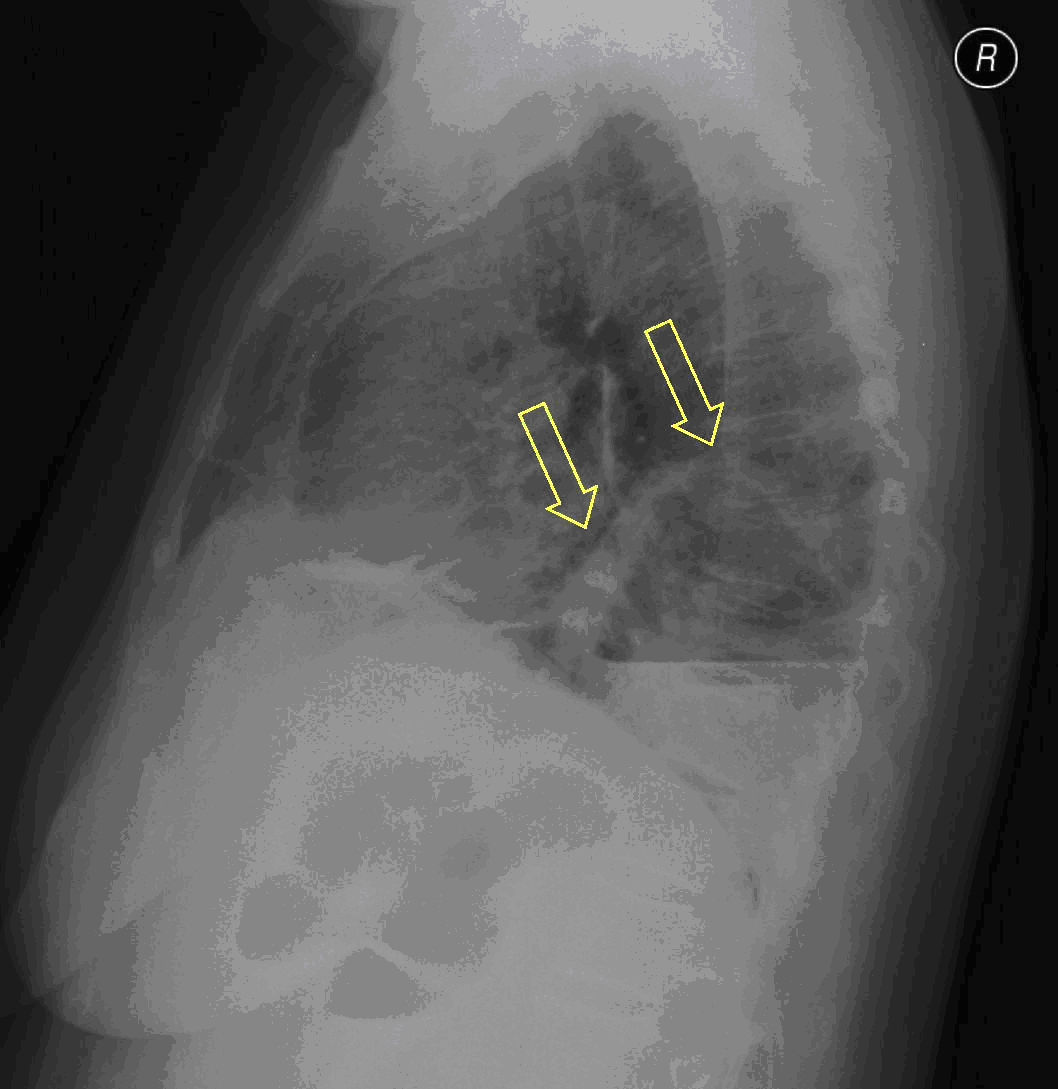

6. e

Image

6. f

e, f.) Chest (PA and right lateral) radiograph: 10 cm large shadow in the RLL, the wall of the „basket sign” measures 0.5 cm + an other one measuring 7 cm possibly with one-two smaller air-fluid levels + small pleural effusion.